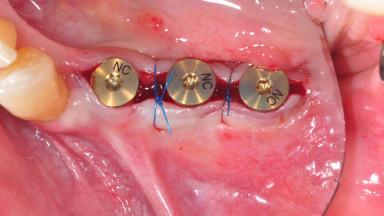

Surgical treatment of a 68-year-old female patient with a distal extension situation in the left mandible. As the CBCT analysis reveals, the bone crest anatomy in the area is not ideal and necessitates an augmentation procedure to achieve a good long-term prognosis for the planned implants and their prostheses.

After the placement of three diameter-reduced two-piece implants the bone is augmented with autologous bone chips and DBBM particles to enlarge the crest volume. The surgery is completed with the application of two membrane layers and primary wound closure.